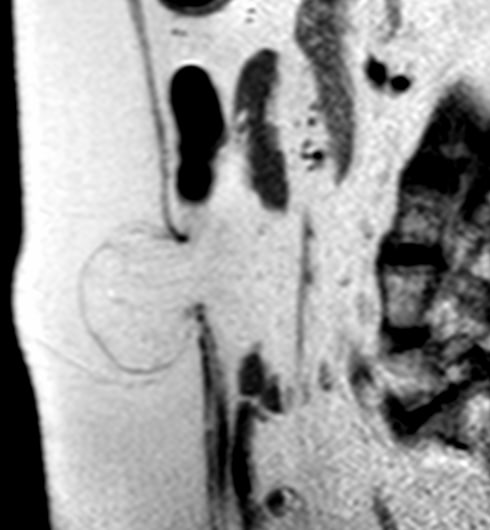

Рутина сегодняшнего дня. Дивертикулит сигмы, нагноение в полости дивертикула с уровнем гной/газ. Стрелка указывает на шейку дивертикула. Яичник прилежит снизу.

Прислали с вопросом: «это эндометриоз?»